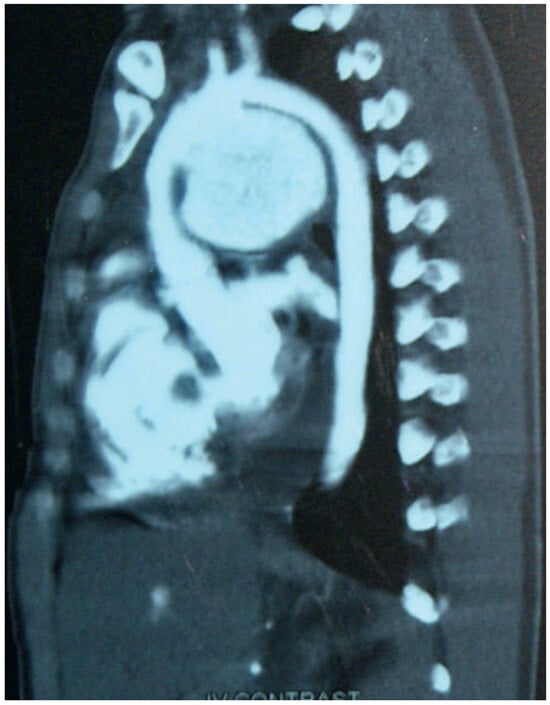

Figure 3. Computes tomography scan 25 days after admission: huge false aneurysm of the ascending aorta.